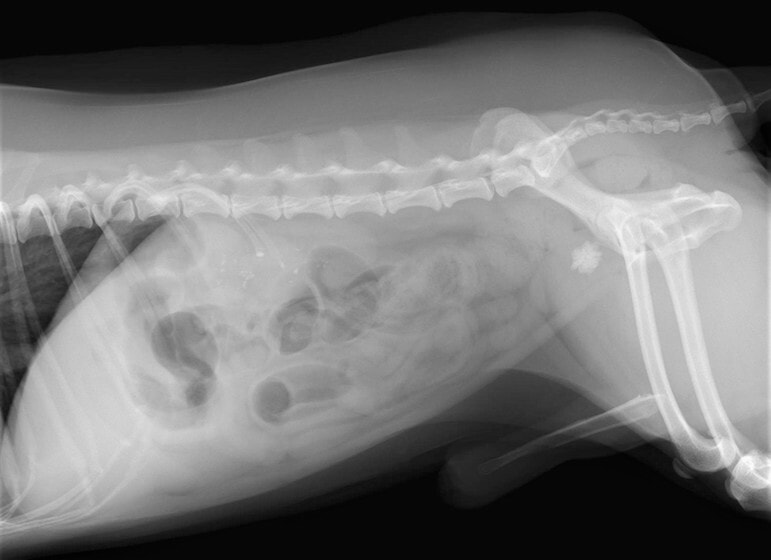

術前のレントゲン

術中写真

左)捻転した胃(右側の赤黒くみられる部分は壊死を起こしています。)

右)腹壁に胃を固定し、再発を防ぎます。

■ 症例:10歳 ドーベルマン 主訴:突然の嘔吐、虚脱